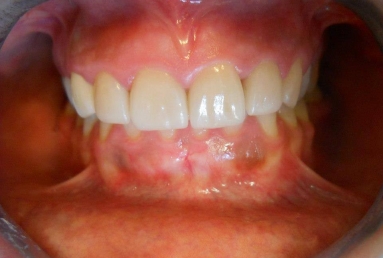

Porcelain veneers on all four upper incisors

Before treatment : inappropriate composite fillings on all four upper incisors, the patient will receive four porcelain veneers.